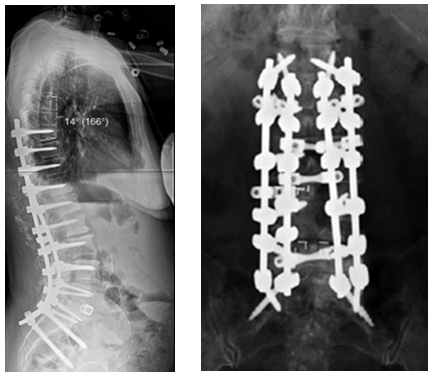

图7 术前-术后1个月-术后1个月外观

图8-11 相关文献表明,钴铬合金可提高固定强度及融合率,防止断棒,但也增加了PJK的发生率